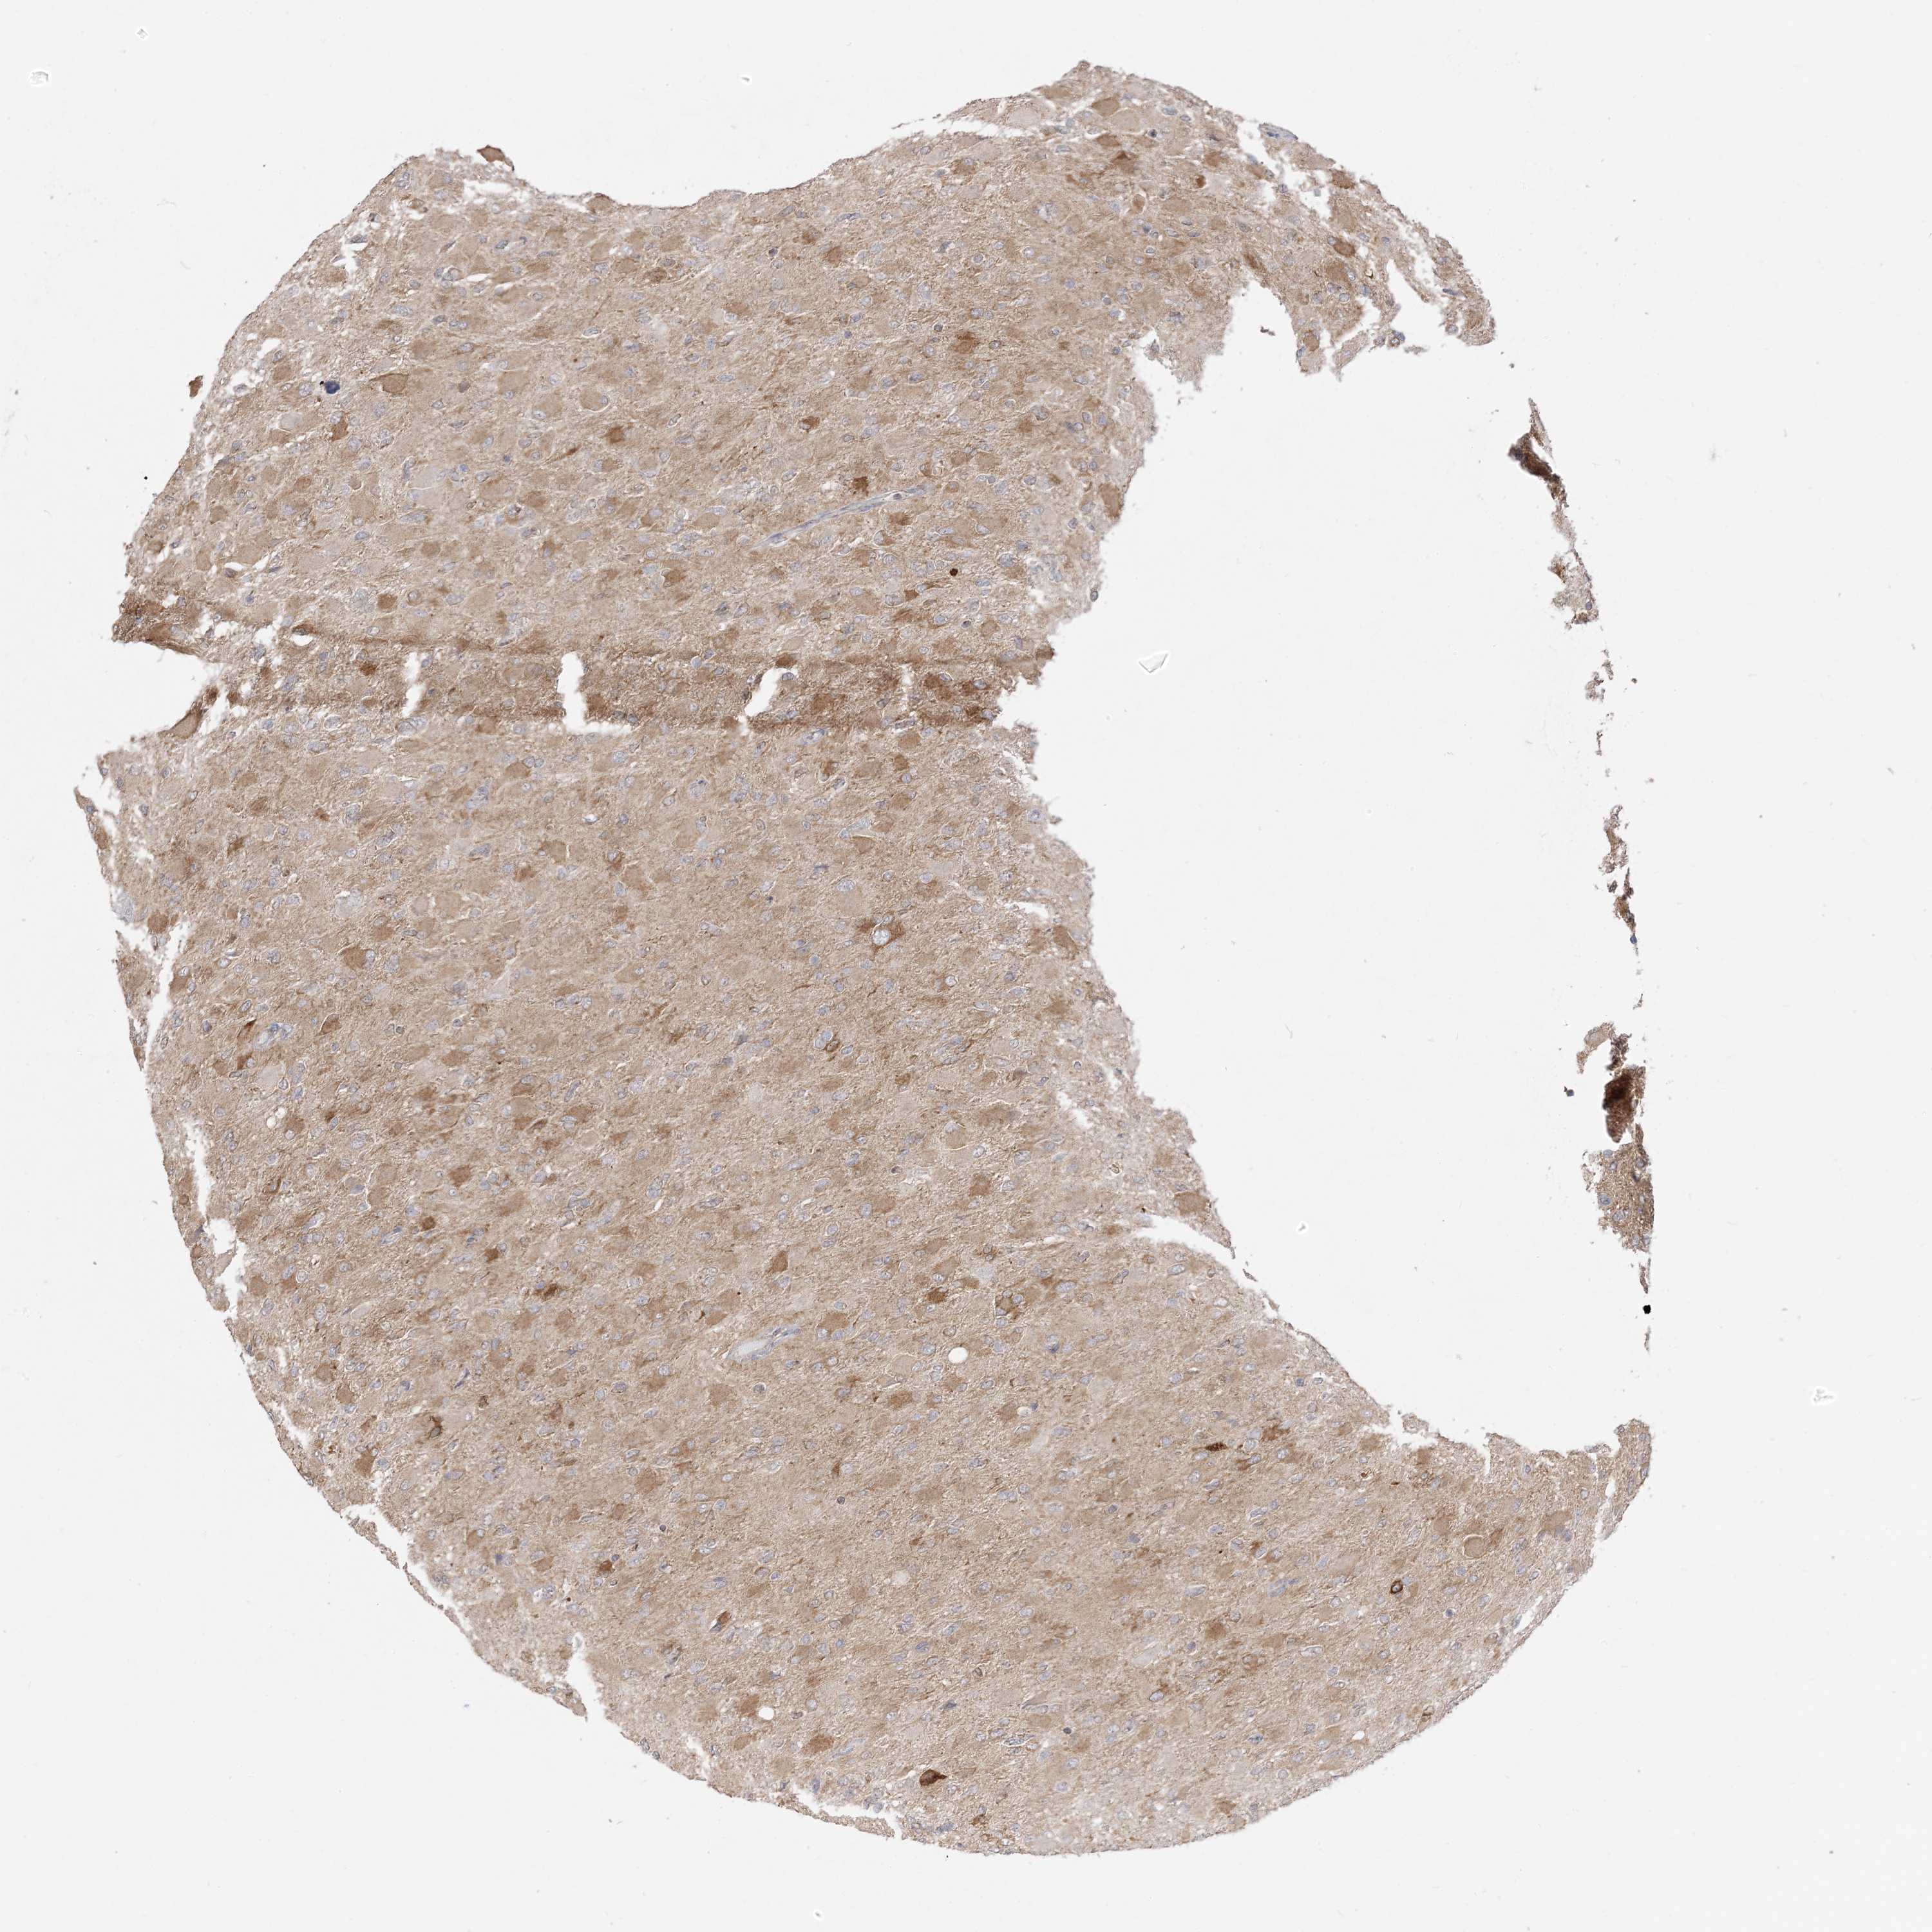

GLIOMA - Protein expressioni

A mouse-over function shows sample information and annotation data. Click on an image to view it in a full screen mode. Samples can be filtered based on level of antibody staining by selecting one or several of the following categories: high, medium, low and not detected. The assay and annotation is described here.

Note that samples used for immunohistochemistry by the Human Protein Atlas do not correspond to samples in the TCGA dataset.

Antibody stainingi

Antibody staining in the annotated cell types in the current human tissue is reported as not detected, low, medium, or high, based on conventional immunohistochemistry profiling in selected tissues. This score is based on the combination of the staining intensity and fraction of stained cells.

Each image is clickable and will lead to virtual microscopy that enables deeper exploration of all samples and also displays staining intensity scores, fraction scores and subcellular localization as well as patient and tissue information for each sample.

Antibody CAB037142

Staining

High

Medium

Low

Not detected

Intensity

Strong

Moderate

Weak

Negative

Quantity

>75%

75%-25%

<25%

None

Location

Nuclear

Cytoplasmic/membranous

Cytoplasmic/membranous,nuclear

Glioma, malignant, High grade

Glioma, malignant, Low grade